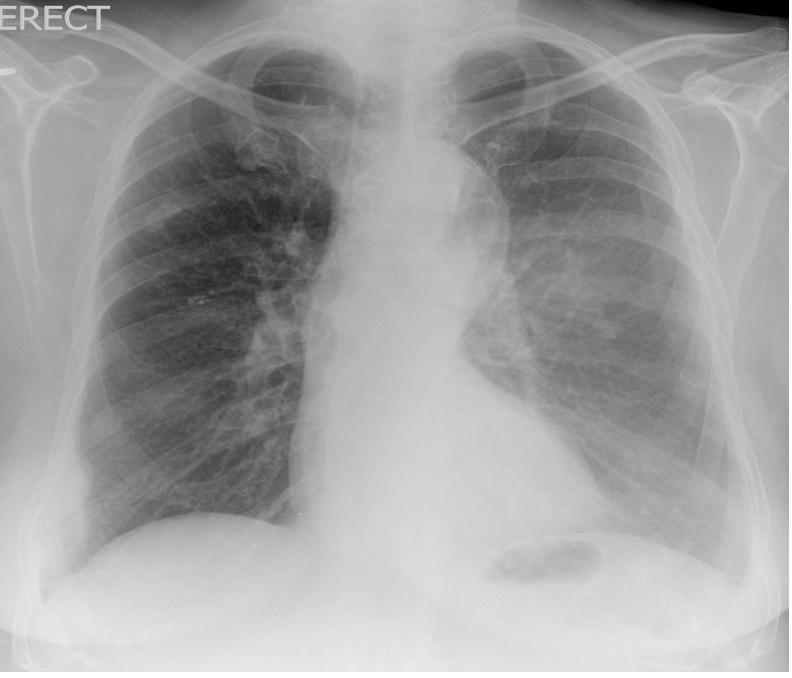

What is this AP CXR showing?

Left Lower Lobe collapse –> Sail sign

Loss of silouette sign of left demidiaphragm and descending aorta

Inferior displacement of left hilum

Inferior displacement of oblique fissue